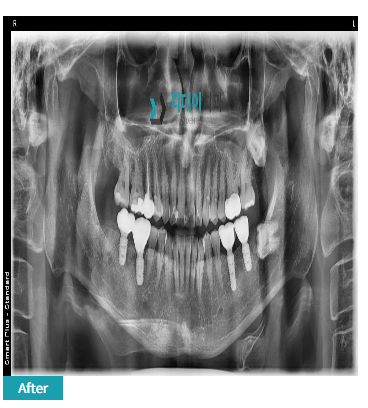

240422

결국 뼈 이식을 먼저 하고 일반 임플란트를 진행하기로 했습니다. 시간은 좀 더 걸렸지만,

결과적으로 더 안전하고 오래 사용할 수 있는 임플란트를 하게 되셨죠.